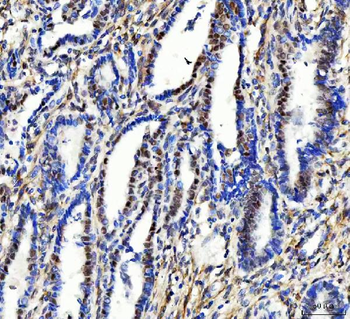

RARB Rabbit Polyclonal Antibody [orb11327]

FC, ICC, IF, IHC-Fr, IHC-P, WB

Bovine, Canine, Gallus, Porcine, Rat

Human, Mouse

Rabbit

Polyclonal

Unconjugated

50 μl, 100 μl, 200 μlTIG2 Rabbit Polyclonal Antibody [orb11481]